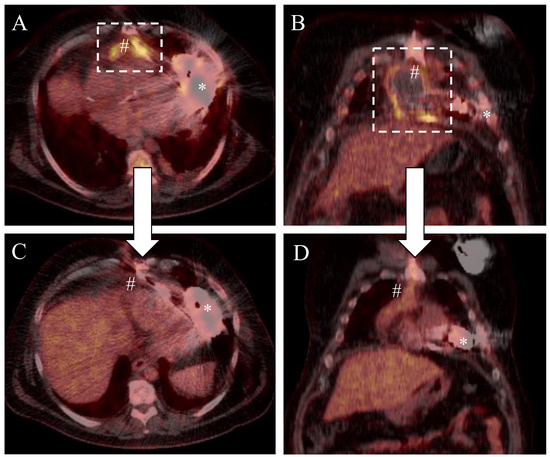

A 49-year-old male patient with a history of dilative cardiomyopathy and end-stage heart failure (NYHA IV, INTERMACS III) underwent LVAD implantation (HeartMate 3, Abbott) and concomitant patent foramen ovale closure in our institution. Indication for LVAD therapy was bridge-to-candidacy, as the patient was additionally suffering from untreated reactive depression. Risk factors for infection were the INTERMACS status, overweight (BMI 34 kg/m2) and insulin-dependent diabetes (Type II). After an uneventful intrahospital clinical course for LVAD implantation, the patient was discharged. However, 6 months after LVAD implantation, the patient was readmitted to the ICU presenting dyspnea, systemic infection signs and left-sided chest pain. Computer tomography unveiled a thoracic empyema and consequently a left thoracotomy was performed for drainage and pleural decortication. Intraoperative bacterial swabs confirmed the presence of staphylococcus aureus (penicillin R > 0.5; levofloxacin I < 0.12). Therefore, in addition to surgery, guided antibiotic therapy (fosfomycin and floxacillin) was initiated. The patient recovered well and could be discharged without antibiotic therapy one month after decortication. Six months later, the patient was again re-admitted to our institution presenting with septicemia with staphylococcus aureus. An integrated positron emission tomography/computed tomography (PET/CT) scan (Biograph mCT, Siemens Healthineers AG, Erlangen, Germany) with the glucose analogue 2-(18)F-fluoro-2-deoxy-d-glucose (FDG) (Figure 1A,B) unveiled two intrathoracic areas of activity enrichment, one surrounding the outflow graft (SUVmax 10.5) and another involving the intrathoracic driveline (SUVmax 11.2). Thus, complex surgical wound management including bacteriophage application was planned for the treatment of this severe infection. Patient consent was obtained for an individual bacteriophage treatment respecting the ethical principles for medical research of the Helsinki declaration.

Sternal wound closure was performed as usual using stainless-steel cerclage wire for bone fixation and absorbable single sutures for the pectoral muscle and subcutaneous tissue. The cutis was closed applying Donati’s suture technique. After an uneventful period of 11 days and further antibiotic therapy (piperacillin/tazobactam 4.5 g, 3×/day), the patient was successfully discharged from hospital. After 3 months, a PET-CT scan (Figure 1C,D) was performed in order to corroborate therapy success. Imaging unveiled a significant decrease in contrast enhancement (outflow graft: SUVmax 7.2, intrathoracic driveline: SUVmax 3.0), suggesting a mitigation of the outflow graft infection. Six months later, the patient was readmitted to our hospital showing a local infection of the driveline exit site with Stapylococcus aureus (Penicillin R > 0.5; Levofloxacin I < 0.12), but without interrelation to the former intrathoracic focus. Since the patient did not show signs of a systemic infection, conservative therapy (local treatment with disinfectants and wound dressing changes) without systemic antibiotic was initiated.

Figure 1. PET-CT scan before (A,B) and after (C,D) complex wound treatment. # Outflow graft of the LVAD-System; * Pump housing of the LVAD (HeartMate 3, Abbott, USA). The dashed rectangle shows contrast enhancement involving the outflow graft as a correlate for device infection.